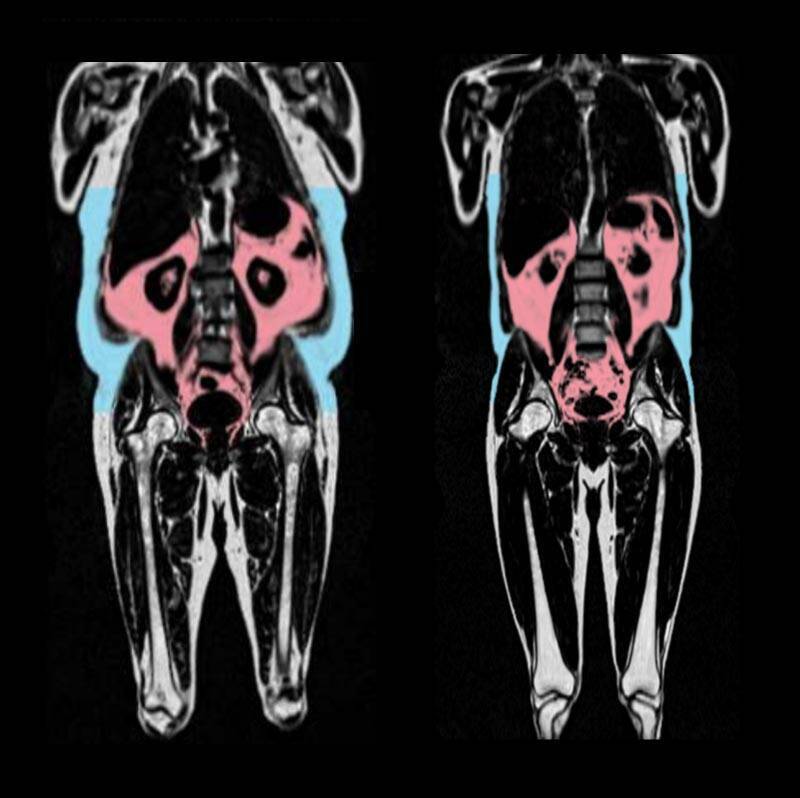

〔編譯陳成良/綜合報導〕根據科學新聞網站《SciTechDaily》報導,一篇發表於權威期刊《歐洲心臟期刊》(European Heart Journal)的最新大型研究發出警訊,指出囤積在腹腔、包圍器官的「內臟脂肪」,是導致心臟加速老化的關鍵元凶;與此同時,研究也發現女性囤積在臀部與大腿的脂肪,反而可能對心臟具有保護作用。

這項由英國醫學研究委員會(MRC)科學家主導的研究,利用了「英國生物樣本庫」(UK Biobank)中超過2萬1000名參與者的數據。團隊採用先進的全身影像掃描技術,並透過人工智慧(AI)分析心臟與血管影像,藉此評估出每個人的「心臟年齡」,並與其真實年齡進行比對。

研究結果明確指出,較高的內臟脂肪量,與心臟加速老化有顯著關聯。這種深藏在腹腔內的脂肪從外表無法直接看出,即便有些人體重正常、身體質量指數(BMI)落在標準範圍,體內仍可能存有大量的內臟脂肪。科學家在血液檢測中發現,內臟脂肪與體內發炎指數升高有關,這被認為是導致器官提早老化的潛在原因。

研究也凸顯了顯著的性別差異。脂肪集中於腹部的「蘋果型」身材,在男性身上是預測心臟提早老化的重要指標。相反地,天生傾向將脂肪儲存在臀部與大腿的「梨形」身材,在女性身上則顯示出對抗心臟老化的保護效果。科學家推測,這可能與荷爾蒙有關,停經前婦女體內較高的雌激素水平,與較緩慢的心臟老化速度有關。